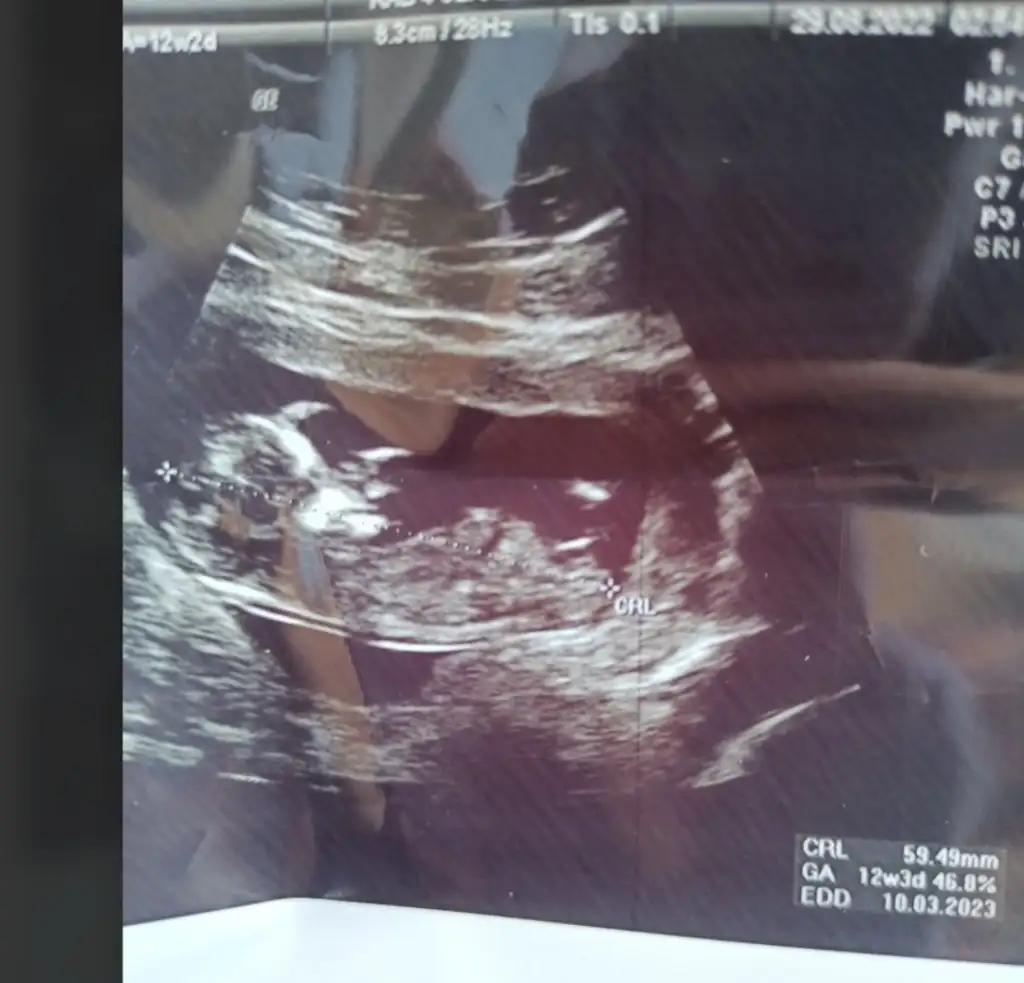

Bana erkek gibi geldi canım sağlıcakla gelsin inşallahMerhaba kızlar ben de Mart annesi olacağım nasipse. 9+3 günlük fotoğrafımız bize de cinsiyet tahmini yapar mısınızEki Görüntüle 3121800